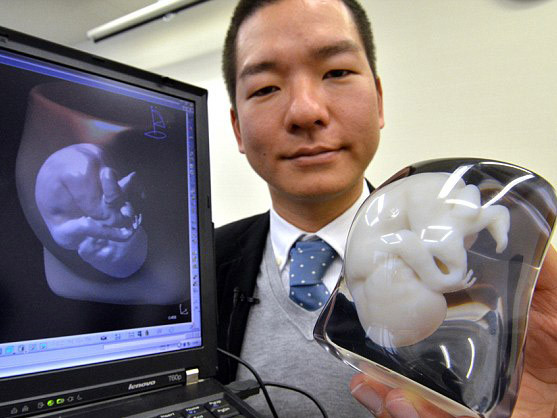

| Mô hình ba chiều của một bào thai được tạo nên nhờ công nghệ in 3D. |

Công ty FASOTEC đã tạo nên mô hình của các thai nhi bằng công nghệ in 3D. Việc dựng mô hình 3 chiều này tương tự như quá trình siêu âm song thay vào đó là dùng máy quét MRI (máy quét cộng hưởng từ).

Công nghệ in 3D này được sử dụng đối với các bào thai từ tám tháng tuổi trở lên.